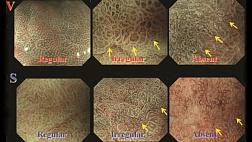

- Классификации

- Атлас